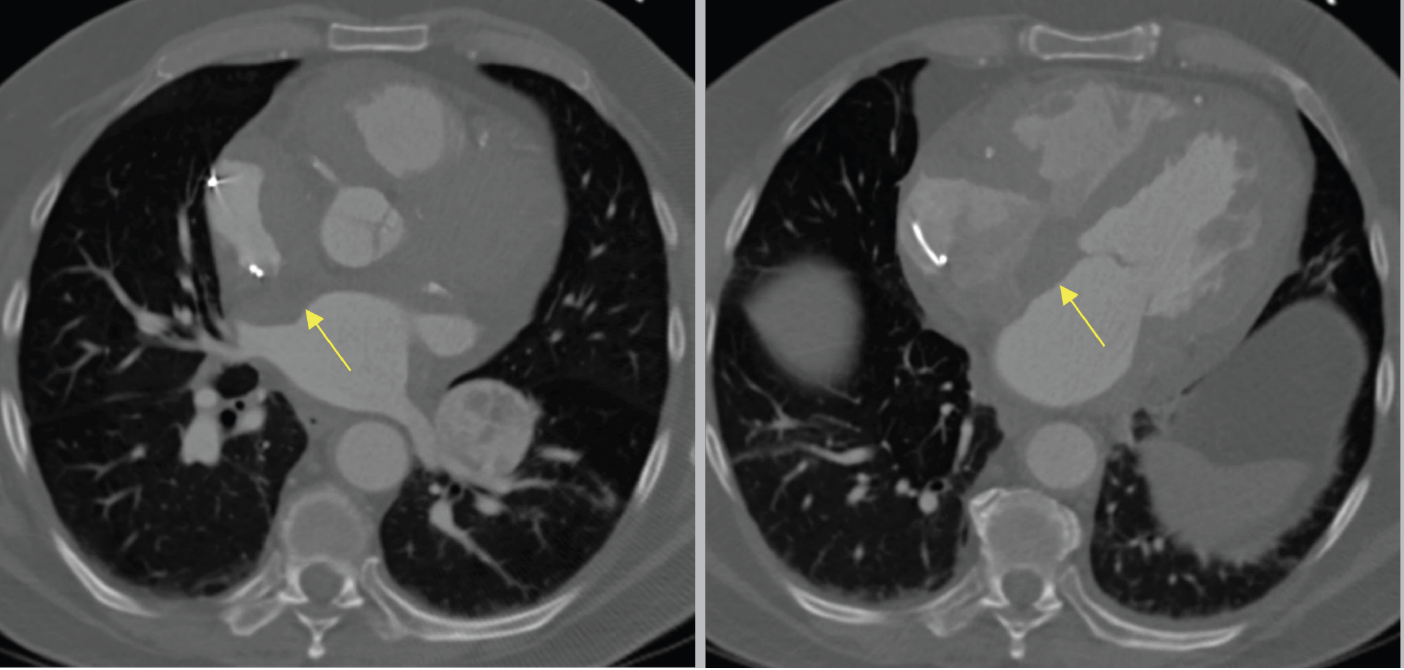

Transesophageal echocardiography at the time of the cardiac biopsy revealed a heterogeneous mass extending along the interatrial septum into the superior vena cava, which appeared partially occluded, as well as probable involvement of the aortic root. A Jawz endomyocardial biopsy forceps bioptome (EMB) (Argon Medical Devices) inserted through an 8.5-Fr Direx steerable sheath (Boston Scientific) was introduced into the RA (Figure 2). The bioptome was steered toward the RA mass at the inferior limbus of the fossa ovalis and several biopsies were obtained. However, the size of the samples was deemed to be insufficient for frozen section analysis. The EMB was then exchanged to a liver access Core needle (Cook Medical) through the steerable sheath and oriented toward the mass in the inferior limbus of the fossa ovalis where several biopsies were obtained. However, pathologic review of the core needle biopsy samples was inconclusive. Then, an endobronchial alligator forceps was used to biopsy the RA mass under intracardiac echocardiographic guidance, with no complications. Pathology was consistent with lymphoid tissue seen in lymphoma (Figure 3).